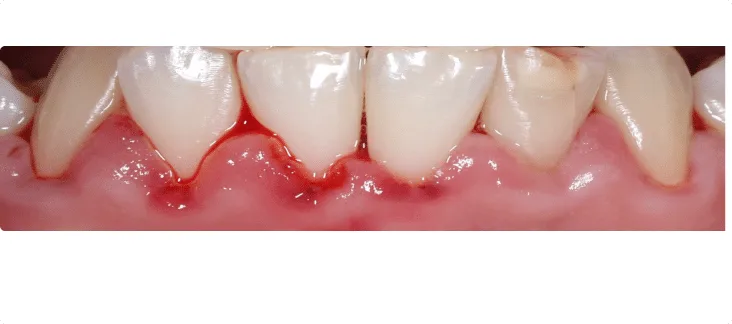

Acute Ulcerative Gingivitis

In acute ulcerative gingivitis, the gum tissue appears swollen, red, and painful, with a shiny surface and bleeding when gently examined. It rarely causes spontaneous bleeding and is usually not painful in its mild forms; however, in acute cases it can be quite uncomfortable.